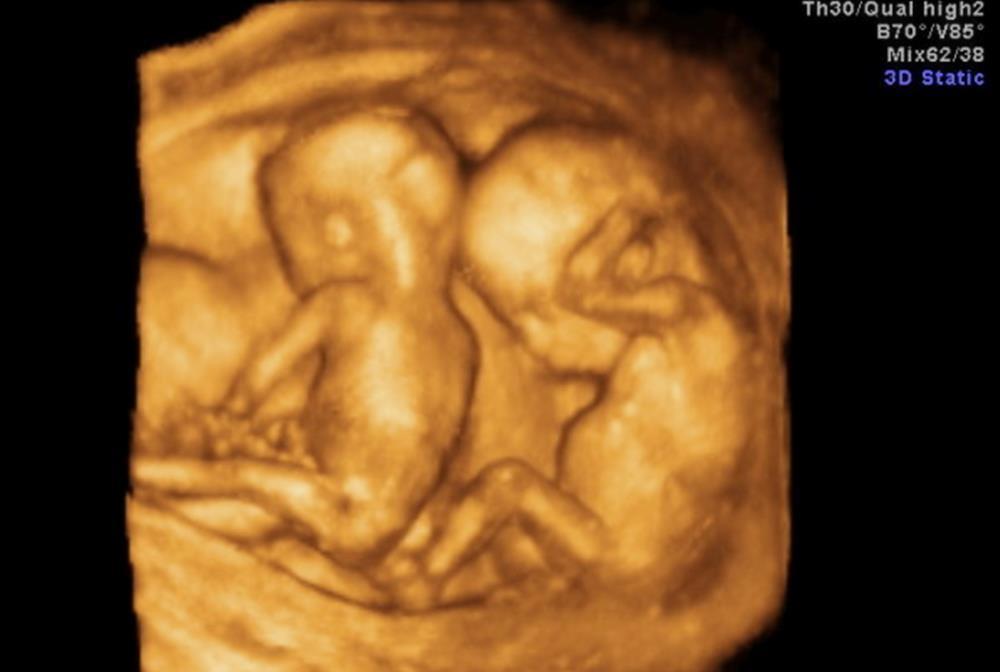

冷知识:做四维彩超的时候,怀双胞胎的孕妈要交“双份钱”

需要说明的一点是,双胞胎并不是每次检查都收“双份钱”,有明确规定:彩超常规检查按部位收费,中晚期妊娠胎儿检查,计价单位为“每胎儿”。

所以说,在中晚期的检查中,才会收双份钱。